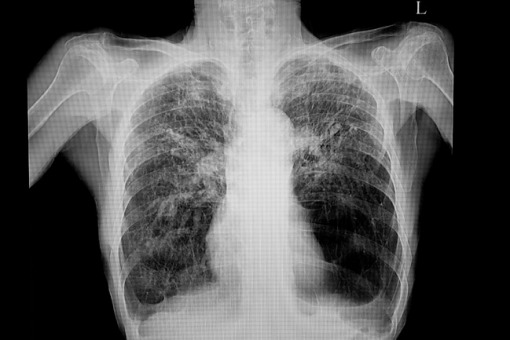

Podsumowanie roku w raku płuca

Prof. Chorostowska-Wynimko o raku płuca – podsumowanie 2024 r. w pneumonologii ►